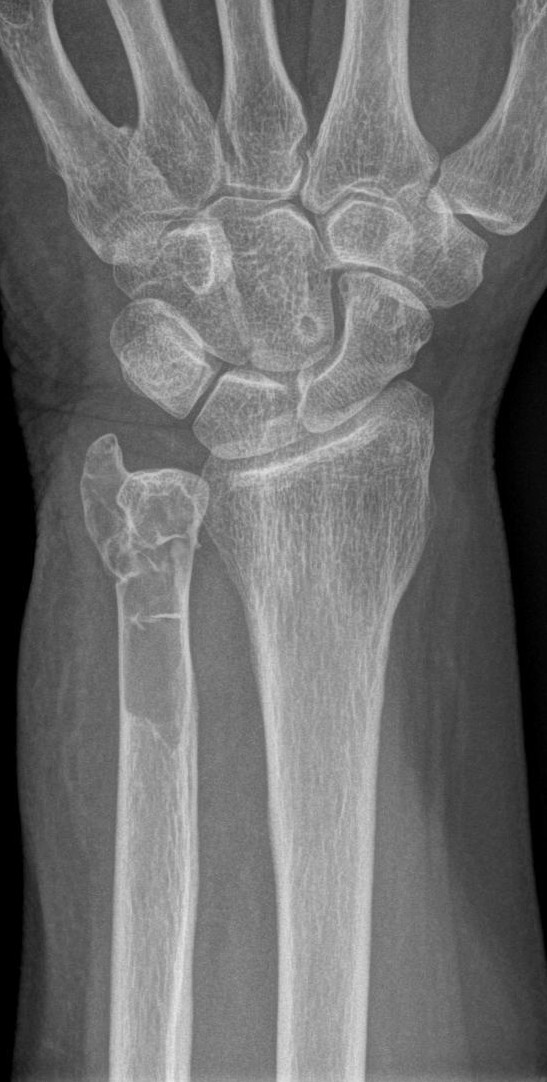

Een 63-jarige vrouw struikelt en breekt haar pols. De fractuur in de distale ulna blijkt door een lytische botafwijking te lopen. Een CT-scan laat geen andere botafwijkingen zien. Behalve een hypercalciĆ«mie en een verhoogde parathormoonspiegel is het laboratoriumonderzoek niet afwijkend.